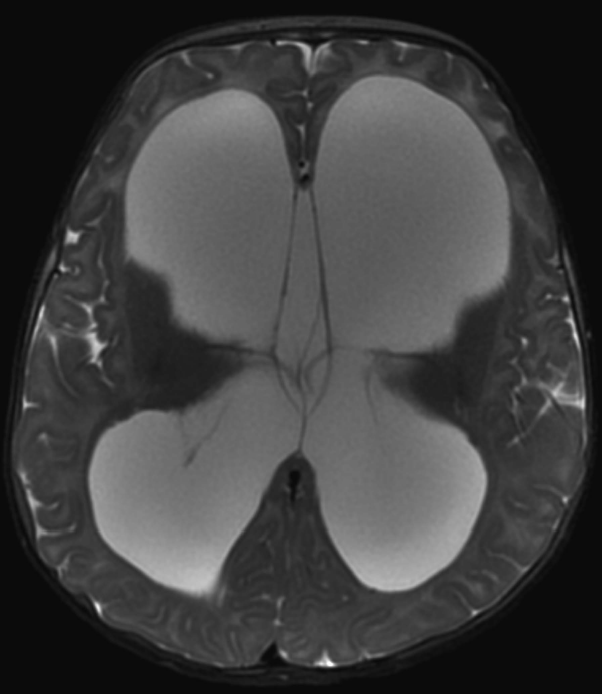

图1:MRI显示脑积水,脑室严重扩张